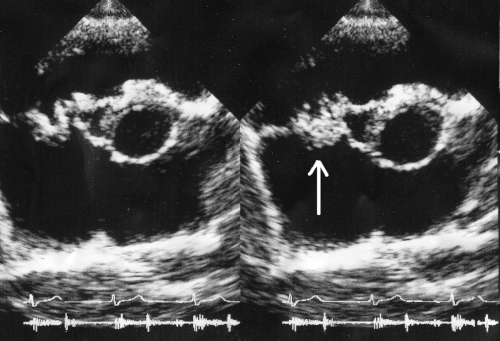

Vegetation on the tricuspid valve by echocardiography. Arrow denotes the vegetation.

In general, the Duke criteria should be fulfilled in order to establish the diagnosis of endocarditis.[11][39] Although the Duke criteria are widely used, they have significant limitations.[11] For example, the sensitivity of the Duke criteria for detecting infective endocarditis decreases when prosthetic heart valves are present.[11]